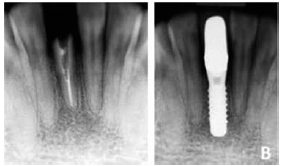

Uma paciente, de trinta e nove anos de idade, procurou atendimento odontológico, queixando-se, principalmente, de comprometimento estético em função da perda da coroa do incisivo central inferior direito. Ela relatou que, havia dez anos, tinha sofrido trauma na região anterior inferior, com consequente fratura coronária, que a levou a tratamento endodôntico e reabilitação protética. Durante a anamnese, constatou-se bom estado de saúde geral, sem relato de uso crônico de medicação nos últimos seis meses nem antecedentes alergênicos ou tabagista. Ao exame físico, constatou-se a fratura do incisivo central inferior lado direito (dente 41) ao nível cervical e ausência de processo inflamatório nos tecidos adjacentes. Oexame radiográfico periapical revelou fratura radicular vertical sem indícios de processo inflamatório periapical, boa quantidade e qualidade óssea, com preservação das cristas ósseas proximais e dentes adjacentes vitais, ou seja, sem alterações radiográficas evidentes, conforme imagens radiográficas (inicial e final) a seguir.

Como a resposta final dos tecidos rígidos e moles é influenciada pela posição entre o implante e a restauração proposta, o diâmetro do implante, o tipo de implante, a posição e o número de implantes devem ser selecionados individualmente, levando-se em consideração a anatomia e as condições no que se refere a espaço.